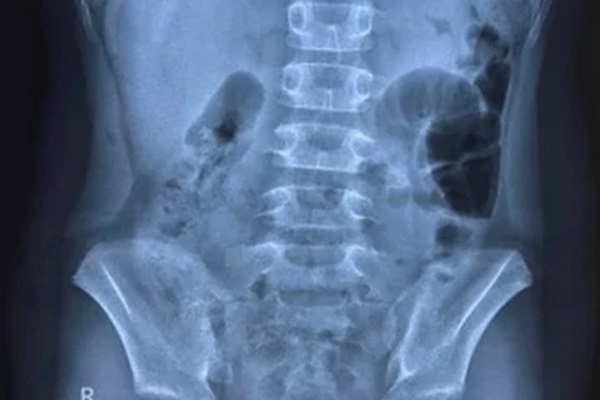

Hình ảnh chụp X-quang cho thấy bệnh nhi có liềm hơi dưới vòm hoành 2 bên, bác sĩ nghi thủng tạng rỗng. Ảnh: Bệnh viện Trẻ em Hải Phòng cung cấp.

Theo hình ảnh chụp X-quang, bệnh nhi có liềm hơi dưới vòm hoành 2 bên. Tại Bệnh viện Trẻ em, bé được chẩn đoán bị viêm phúc mạc do thủng dạ dày/mắc Covid-19.